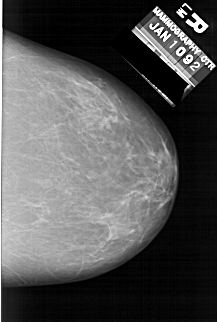

A_1634_1.RIGHT_MLO

RIGHT_MLO LINES 6121 PIXELS_PER_LINE 4006 BITS_PER_PIXEL 12 RESOLUTION 43.5 NON_OVERLAY